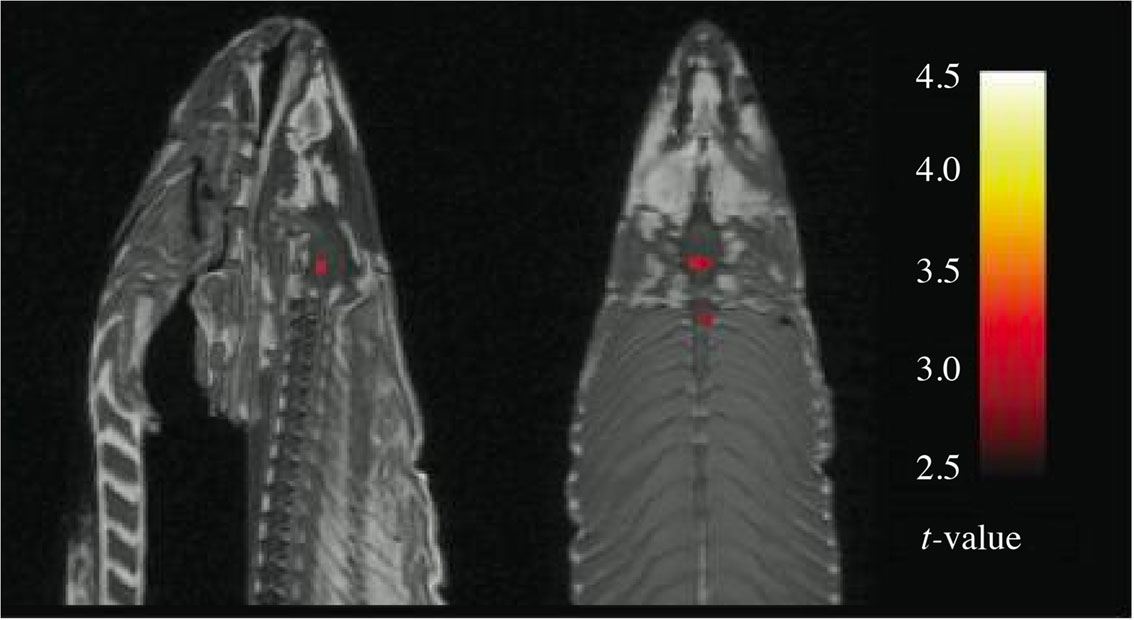

Jo Røislien skriver at bildet av den døde laksen viste «tre statistisk signifikante prikker» (1).

Menes at bildet viste tre områder hvor det før og etter stimulering var en forskjell i signalstyrke (longitudinell studie), eller kun en forskjell i signalstyrke mellom forskjellige anatomiske områder (tversnittstudie)? Presiseringen er helt avgjørende for å vurdere dette funnet. I en tversnittstudie kan en forskjell i prikkene vise reelle kjemiske forskjeller, også hos en død laks.

Begrepet «statistisk signifikant» er vanligvis knyttet til en p-verdi. I dette tilfellet synes imidlertid ordet «signifikant» å være knyttet til en t-verdi. T-verdier er en form for kvantifisering av forskjeller, altså et litt komplisert effektestimat som er uavhengig av antall observasjoner. P-verdien derimot, er sterkt avhengig av antallet slik at ubetydelige forskjeller blir signifikante bare antallet observasjoner er stort.

Eva Skovlund skiller mellom p- og t- med følgende formulering: «Skal man vurdere klinisk relevans, gir et effektestimat … mye mer informasjon enn en p-verdi» (2). Videre vurdering av effektestimater krever biologisk og eller medisinsk innsikt.